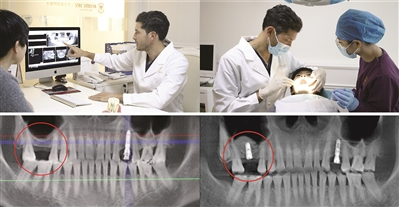

5分钟种好一颗牙 刚下手术台即刻吃东西

来自天河区、今年57岁的左姨,一颗大牙缺失。她想做种植牙,但一来担心太痛,身体承受不了;二来担心种牙恢复期没牙用很不方便。种牙节期间,她找到德国生长因子种植牙技术专家米歇尔博士。在了解左姨口腔情况后,米歇尔博士为其定制了一套种牙方案。“使用德国新技术的整个过程很舒适,自身的东西用到自己口腔里很安全。没种牙之前担心很痛,种完之后觉得担心多余了,其实一点都不痛,5分钟就种完了,很轻松,刚下手术台就可吃些松软食物。”左姨说。

德国生长因子种植牙技术 “快速恢复”新体验即种即用

临床上类似左姨这类患者很多,担心做种植牙太折腾,恢复期间没牙用。其实,德国生长因子种植牙技术的应用为口腔种植开启了快速恢复新体验。米歇尔博士介绍说,德国生长因子突出的特点是可以提升凝血功能,减少出血量,加快骨细胞增殖速度,让戴牙等待时间缩短1/3,而且100%自体提取,无排斥反应,大大提升种植成功率。此外,该技术适用于各类种植适应症,种植手术同期即可制备完成,新技术的推广可让羊城缺牙市民可更轻松快速种好牙。